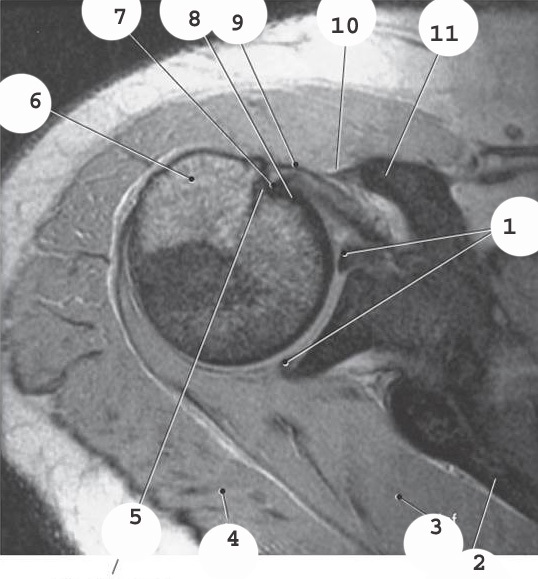

1

bicep

labrum

3

infraspinatus muscle

4

deltoid

2

acromion

teres minor muscle

5

8

subscapularis muscle

10

supraspinatus muscle